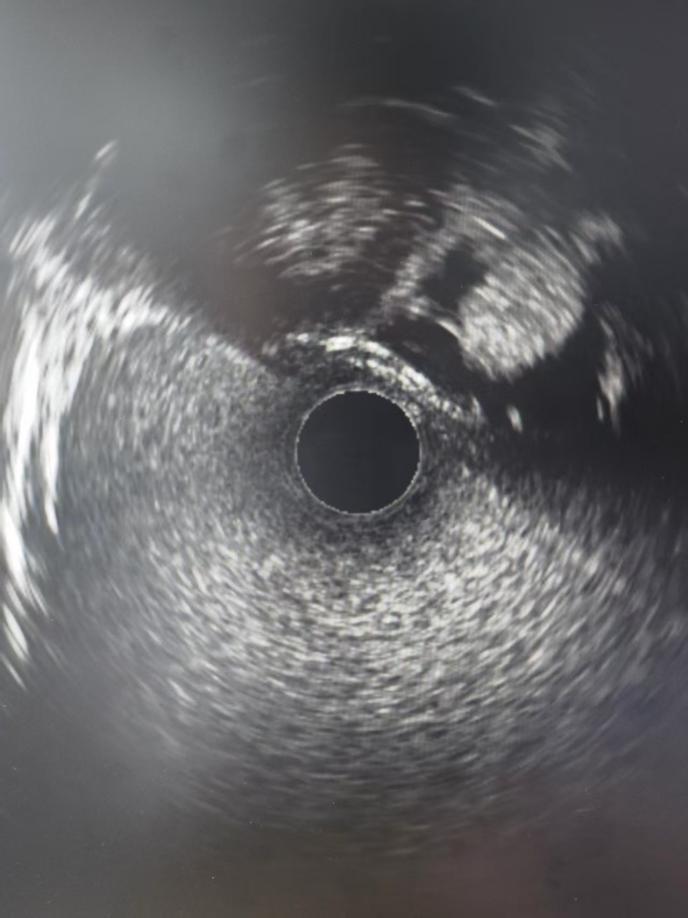

神经内二科团队分析讨论后,为患者实施了静脉窦造影术+测压+血管内超声检查。造影提示右侧横-乙状窦交界区局限性狭窄,测压提示狭窄近-远端压力差3 mmHg,血管内超声探及静脉窦内多个类圆形凸起,提示内源性狭窄,考虑蛛网膜颗粒所致局限性狭窄。

特发性颅内高压(IIH)的病理生理学可能受到脑窦内结构变化的影响,而特发性颅高压伴静脉窦狭窄包括内源性和外源性两种形态类型。相比于其他检测手段,血管内超声能够提供更真实、准确的静脉窦腔内成分描述,有助于更深入了解特发性颅内高压特点,为该类患者静脉窦狭窄的血管内介入治疗提供有价值的支持。血管内超声(IVUS)可观察到各种类型狭窄,并进行描述性分析,显示了血管内超声(IVUS)在鉴别内、外狭窄类型,内源性狭窄腔内成分和壁内成分方面的潜力。